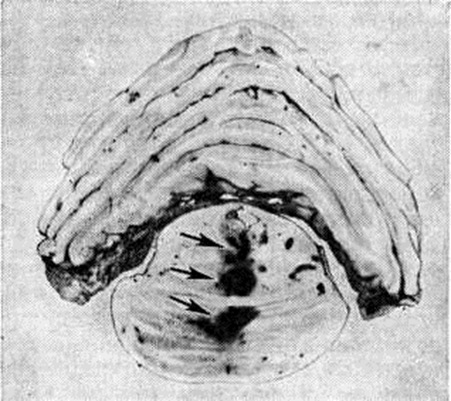

Геморрагический инсульт, как правило, возникает при заболеваниях, протекающих с повышенным артериальное давление. Это обусловлено тем, что сосудистые кризы (смотри полный свод знаний), характерные для гипертонической болезни (смотри полный свод знаний) и артериальной гипертензии (смотри полный свод знаний Гипертензия артериальная), приводят к морфологический изменениям стенок внутримозговых сосудов с нарушением их проницаемости — плазматическому пропитыванию (рисунок 1), некрозам (рисунок 2), образованию микроаневризм (рисунок 3) и их разрывам. Разрыв врождённых артериальных и артериовенозных аневризм может протекать на фоне нормального давления. Преимущественная локализация и характер геморрагий определяются особенностями ангиоархитектоники различных отделов мозга. При гипертонической болезни наиболее тяжёлым изменениям подвергаются сосуды подкорковых узлов и зрительного бугра. Это объясняется отхождением глубоких ветвей под прямым углом от средней мозговой артерии, являющейся продолжением внутренней сонной артерии, и незначительным числом анастомозов сосудов в этой области. В связи с этим на вскрытии кровоизлияния наиболее часто (40%) обнаруживаются в подкорковых узлах с распространением в прилежащее белое вещество (так называемый латеральные кровоизлияния, то есть расположенные латерально от внутренней капсулы, рисунок 4). Второе место по частоте (16%) занимают обширные кровоизлияния, разрушающие подкорковые узлы, внутреннюю капсулу, зрительный бугор (так называемый смешанные кровоизлияния — рисунок 5). Кровоизлияния в зрительный бугор (так называемый медиальные — рисунок 6) составляют 10%, в мозжечок — 6—10%, в мост мозга — 5% от общего числа внутримозговых геморрагий. Кровоизлияния только в белое вещество полушарий мозга встречаются крайне редко. Подразделение полушарных кровоизлияний на латеральные, медиальные и смешанные имеет особое значение в связи с хирургическим лечением геморрагического Инсульт.

Кровоизлияния типа геморрагического пропитывания возникают преимущественно в зрительных буграх, реже в мосту мозга и составляют 15% внутримозговых кровоизлияний. Они являются результатом слияния мелких очагов кровоизлияний, возникающих путём диапедеза из мелких сосудов, имеют вид очагов красного цвета, дряблой консистенции и в силу внешнего сходства иногда напоминают геморрагический инфаркт. В первые часы Инсульт нарушается проницаемость сосудов на границе с кровоизлиянием, развивается отёк; кровь распространяется по ходу нервных волокон. К концу первых суток наблюдаются лейкостазы и лейкодиапедез, размеры очага увеличиваются за счёт диапедезных геморрагий и некробиотических изменений в отёчном веществе мозга. Через двое суток начинается процесс репарации — появление зернистых шаров и гипертрофированных астроцитов; позже образуется вал из астроглии и новообразованных сосудов, кровь подвергается гемолизу, появляются макрофаги с гемосидерином, образуются аргирофильные и коллагеновые волокна. Исходом кровоизлияния может быть формирование глиомезодермального рубца или кисты, содержащих гемосидерин (рисунок 9). В 80—85% кровоизлияний на вскрытии выявляется прорыв крови в желудочки, значительно реже — в подпаутинное пространство. В последнее кровь может также проникнуть из четвёртого желудочка. Первичные вентрикулярные геморрагии нетравматического генеза — явление казуистическое. При разрыве врождённых аневризм артерий основания мозга возникают первичные субарахноидальные кровоизлияния, которые обычно локализуются на базальной поверхности или в латеральной борозде; иногда кровь проникает в субдуральное пространство; часто повреждается вещество мозга (субарахноидально-паренхиматозные кровоизлияния). Расположение гематом, образующихся при этом, зависит от локализации аневризмы, обычно это базальный отдел лобной доли или височная область. В части случаев при незначительном субарахноидально-паренхиматозном кровоизлиянии возможен массивный прорыв крови в желудочки (рисунок 10), что иногда ошибочно диагностируется как первичное вентрикулярное кровоизлияние.